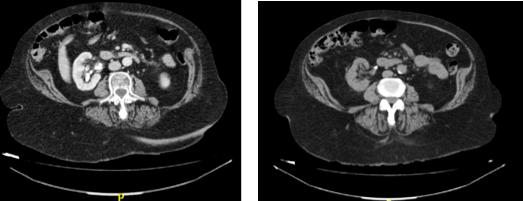

Funding: None

Authors’ contributions: M A A D , W D C M , A M T

Acknowledgments: None

REFERENCES